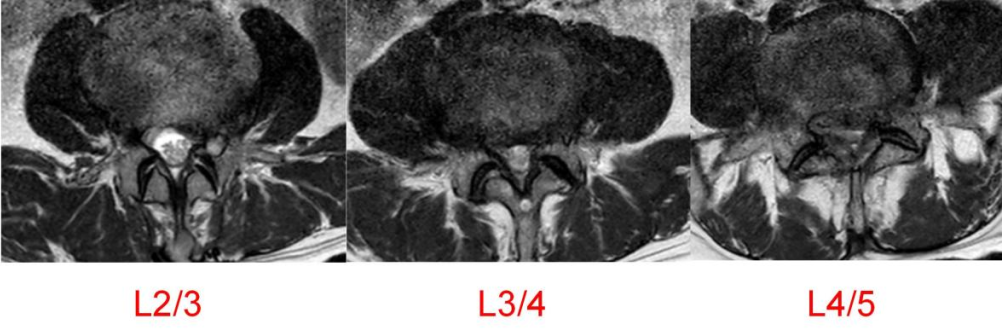

64岁的邱某因“腰痛多年,加重伴左下肢放射痛1月”来到昆山市中医医院脊柱骨科陈勇主任门诊就诊,经对患者的评估后,陈勇主任考虑其为“腰椎间盘突出症、腰椎椎管狭窄症”,随即安排住院治疗。

入院后,陈勇主任在科室组织了病例讨论并表示:常规保守治疗只能缓解症状无法从根本上解决病根。目前,患者已保守治疗1月,症状未见明显缓解,且进行性加重。影像学可见腰椎间盘突出伴椎管狭窄严重程度高,有明确的手术指征,结合患者及其家属的意愿,选择腰椎后路减压植骨融合内固定术。

▲术前MRI

然而患者需行多节段腰椎融合

如何规避神经损伤风险?